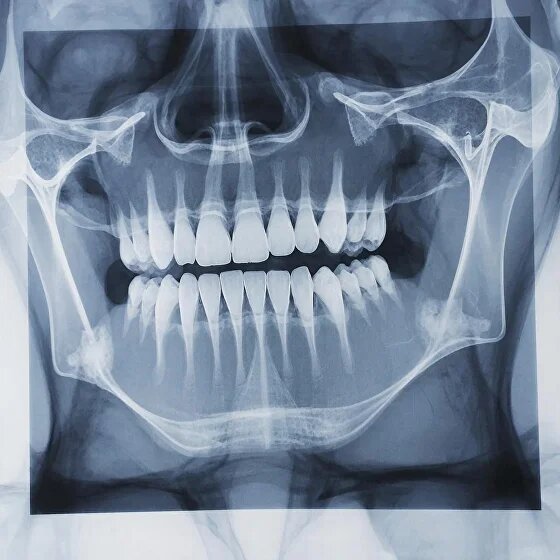

Рентген в стоматологии: зачем он нужен и как проводится

Современная стоматология невозможна без точной диагностики, а одним из самых информативных методов исследования является рентген зуба. В клинике «Ранд» в Новосибирске наши пациенты могут быть уверены: можно делать рентген зуба быстро, безопасно и с максимальной информативностью для врача. Поэтому вопрос делают ли рентген зубов при осмотре — не просто формальность, а важная часть диагностики. В клинике Ранд мы рекомендуем рентген при планировании лечения, перед удалением зуба, перед установкой имплантов и в ряде других случаев, когда визуального осмотра недостаточно.Часто на первый взгляд кажется, что всё в порядке — зубы внешне здоровы. Но только специалист, изучив рентген снимок зубов, может увидеть:кариозные полости между зубами;

скрытые воспалительные процессы (например, в каналах корней);

ретинированные (не прорезавшиеся) зубы;

состояние костной ткани;

последствия травм.

Как делают рентген зуба?

Современное оборудование позволяет получать чёткое изображение при минимальной нагрузке на организм, что делает рентген зуба безопасным для взрослых и детей.Многих пациентов интересует: как делают рентген зуба и безопасно ли это. Процедура в нашей клинике проходит следующим образом:Пациента просят надеть защитный фартук.